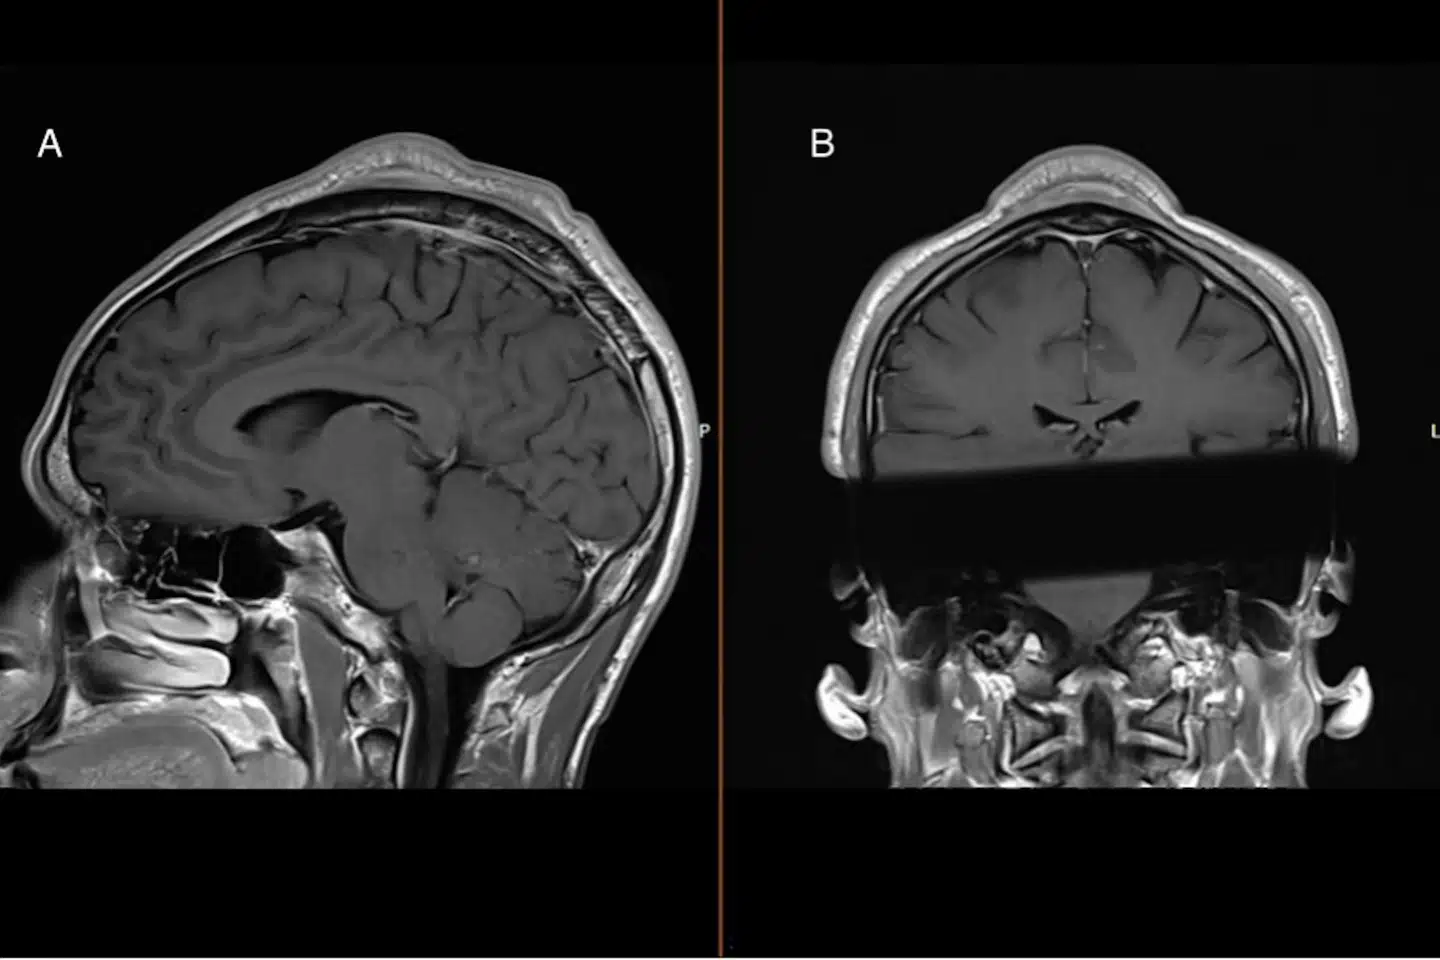

I 19 år havde den 30-årige danske mand drejet rundt på sit hoved som en fast del af sin dansetræning.

Men det skulle vise sig at få konsekvenser.